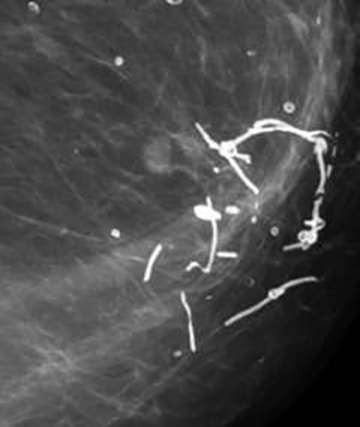

![]() Suture Calcifications: These represent calcium deposited within suture material, and appear linear or tubular and may outline surgical knots.